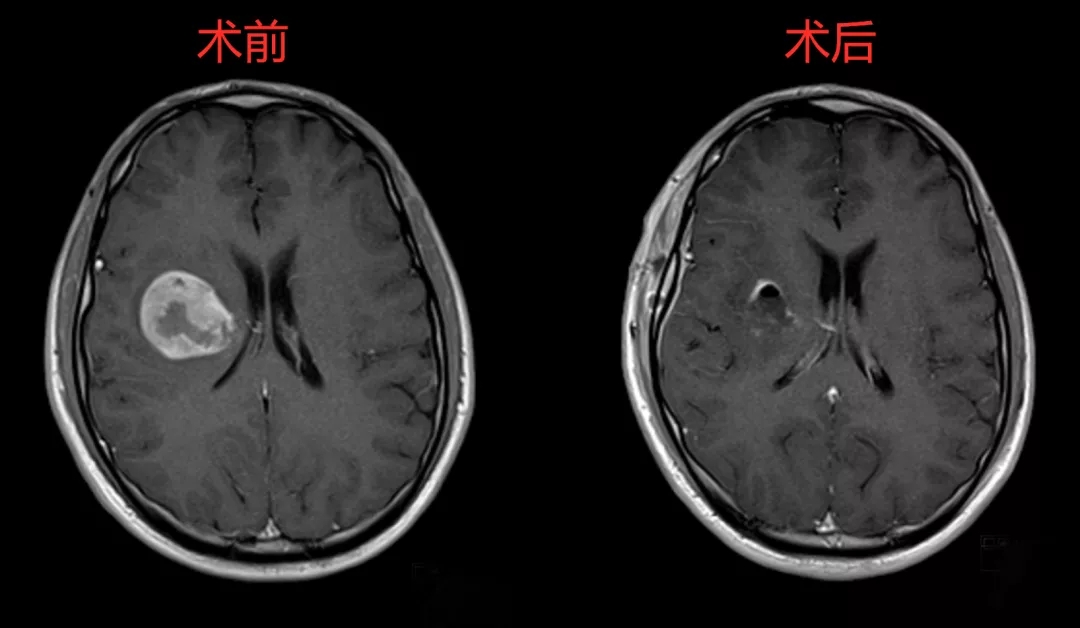

近日,葡萄牙Hospital Gaia Espinho神經外科主任Antonio Marques Baptista醫生完成了首例在顯微鏡和球囊造通輔助下側腦室膠質瘤切除術,切除了一個44x30毫米大小的惡性膠質瘤。術后患者恢復良好,神經功能正常。

術后,患者意識清醒,語言等功能都恢復良好,身體正順利康復中。